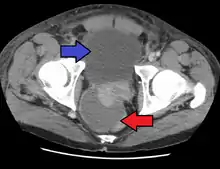

Abscess of the prostate (red arrow) resulting in urinary retention (blue arrow)

Severely ill patients may need hospitalization, while nontoxic patients can be treated at home with bed rest, analgesics, stool softeners, and hydration. Men with acute prostatitis complicated by urinary retention are best managed with a suprapubic catheter or intermittent catheterization. Lack of clinical response to antibiotics should raise the suspicion of an abscess and prompt an imaging study such as a transrectal ultrasound (TRUS).[7]